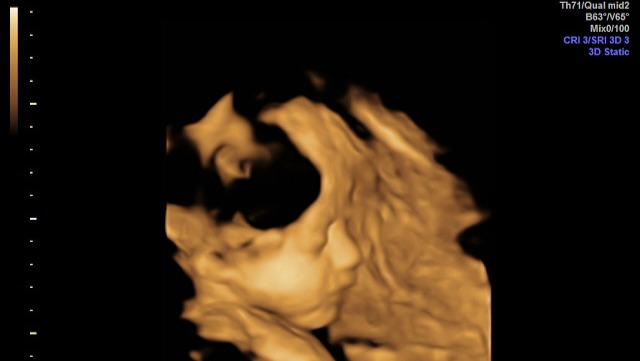

When we were expecting our daughter, Zarah Angelica, we were already parents to three children. Throughout the pregnancy, we attended numerous ultrasound examinations due to gestational diabetes and risk of preeclampsia. We were repeatedly told that everything looked normal and that we were expecting a healthy baby. Because of this reassurance, we brought our children with us to one of the later ultrasounds, but this time finally a 3D ultrasound, wanting them to share in the joy and anticipation of welcoming a new sibling and see her beautiful face.

During that ultrasound, we were told that Zarah Angelica was missing her corpus callosum, a vital structure in the brain with 200 million connections between the hemispheres of the brain. With all of our children present, the message we had trusted was suddenly replaced by devastating news. What was meant to be a moment of shared happiness became the beginning of a life-altering reality for our entire family. I still can't understand why the hospital hadn't discovered this after 10 ultrasounds. I knew my body couldn't really handle another pregnancy, I was told at my last birth that my body needed a break because of my health. We agreed that if the baby wasn't healthy, we couldn't gamble with two lives. So it was important to know the baby was healthy.